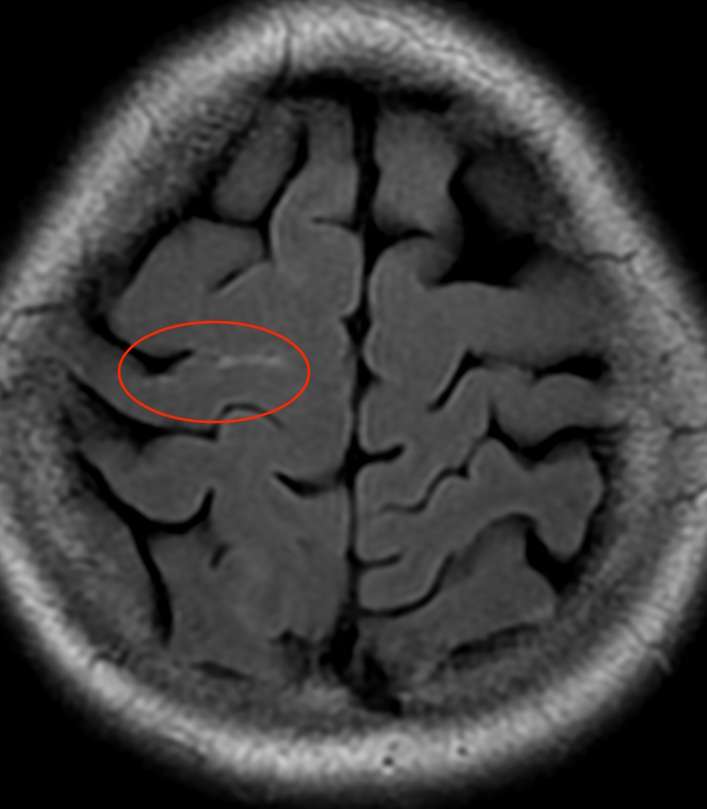

頭部MRI検査では、

脳のすき間の一部が白くなっており、少量の血液である事が分かります。

つまり、円蓋部という場所のくも膜下出血です。